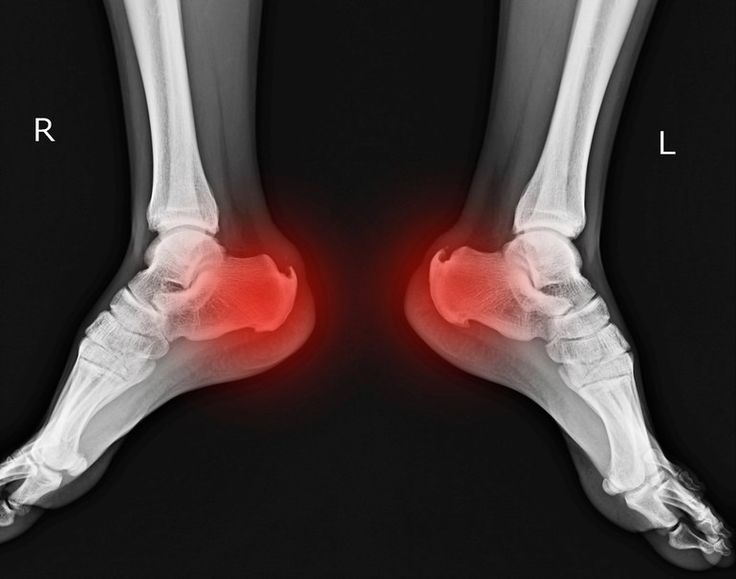

Diagnosis of Complex Fractures

Understanding how the injury happened

Checking pain, swelling, and movement

X-rays to identify the Bone fracture

CT scan or MRI for complex injuries

What imaging tests are used to diagnose complex fractures?